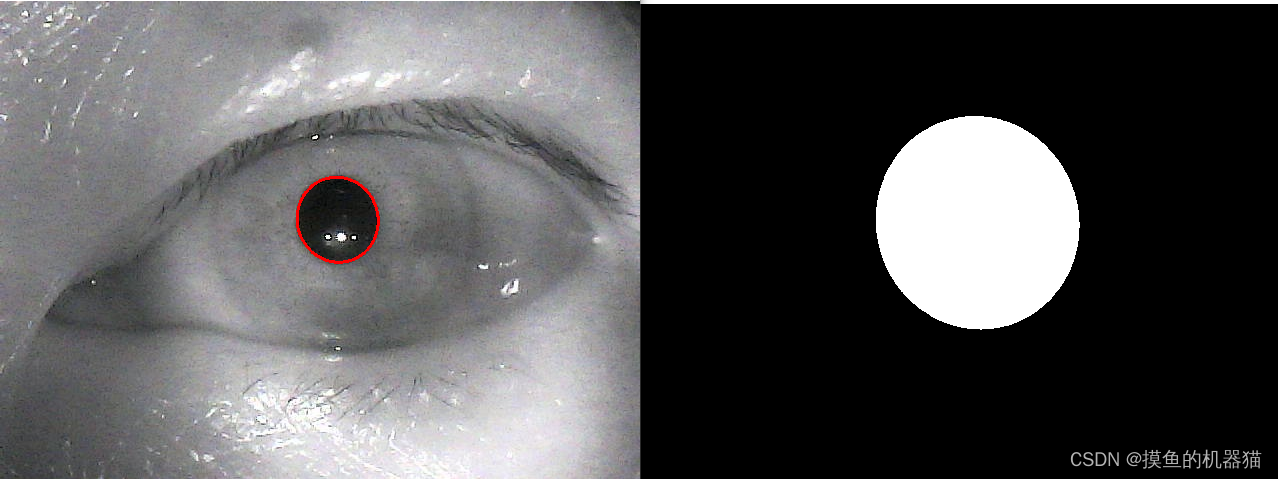

读取后的图片如下所示

进行二值化后得到以下图像,可以看到瞳孔中存在黑洞,其他区域存在白色干扰点。

先找到图像中最大面积的连通域,然后进行闭运算,最终得到的结果如下所示

然后获取轮廓并进行椭圆拟合,然后将拟合的椭圆绘制在原图与mask上(画在原图上的椭圆要使用原始值,而画在mask上的椭圆需要对长轴和短轴值进行放大,使其能尽可能的盖住虹膜区域)